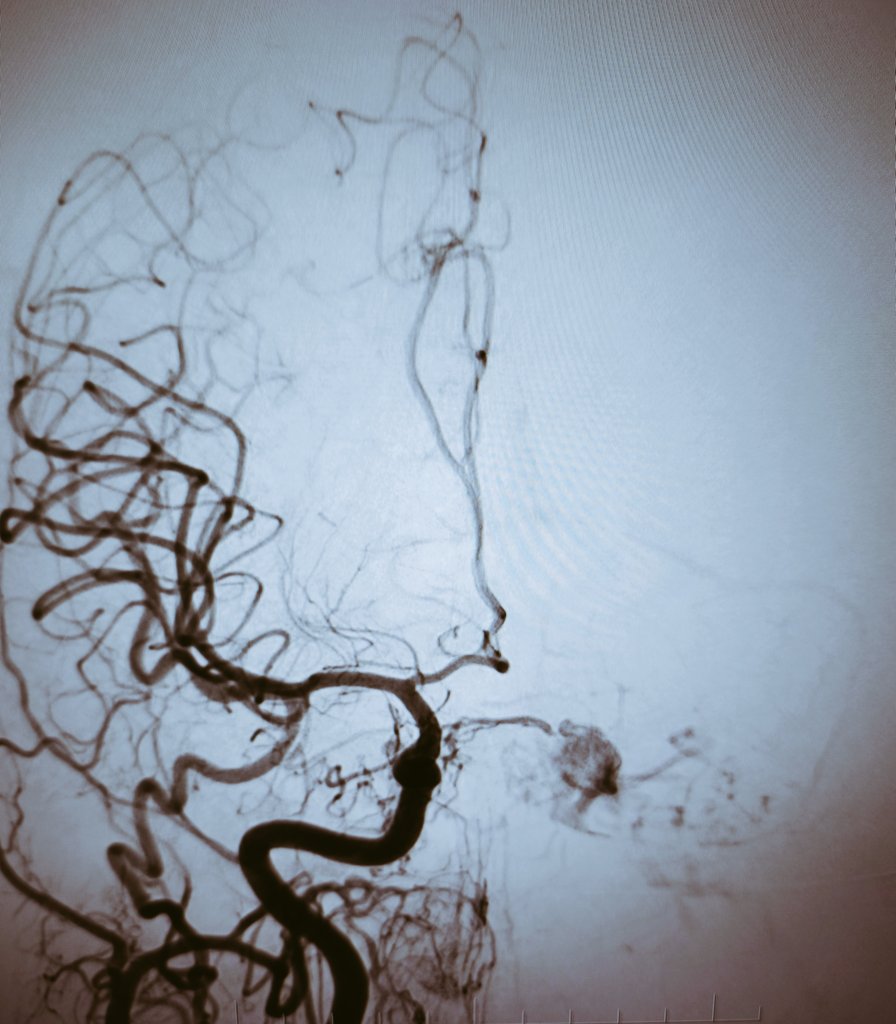

Distal M2 occlusion NiHSS 10. Complete recanalization using RED43 (@penumbrainc) aspiration catheter. NIHSS 2 at 24h.

English